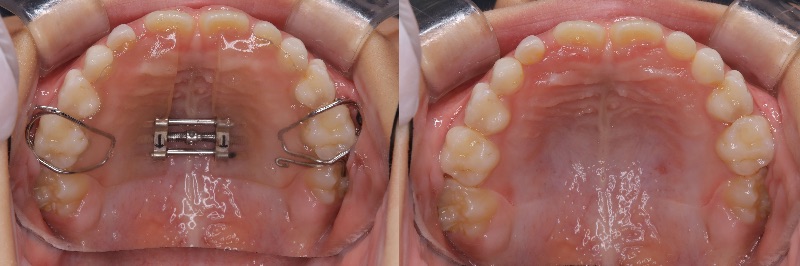

スマーティチェックのチェックをお願いします。

S様

右側のスピーの湾曲が強く、親知らずの抜歯も拒否されています。

右上5番、4番は圧下を組み込んでいます。

適正であるか見ていただけますでしょうか?